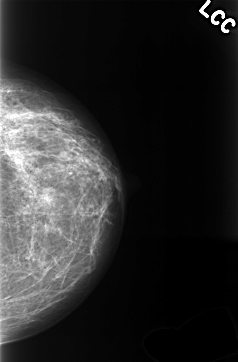

C_0363_1.LEFT_CC

LEFT_CC LINES 4344 PIXELS_PER_LINE 2856 BITS_PER_PIXEL 12 RESOLUTION 50 NON_OVERLAY